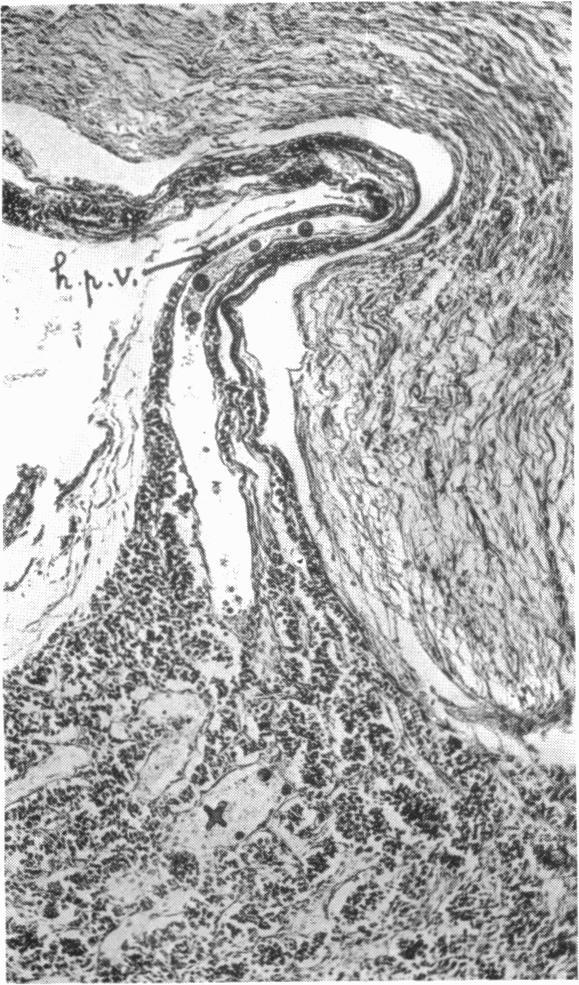

Hypophysio-Portal Vessels and their Colloid Accompaniment.

J Anat. 1933 Jan;67(Pt 2):227-232.1.